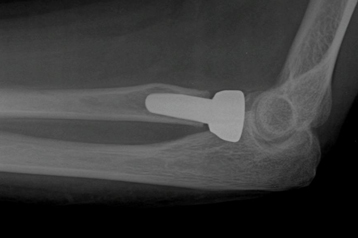

Post-Surgery

Repair of Non-Union With Plates and Screws